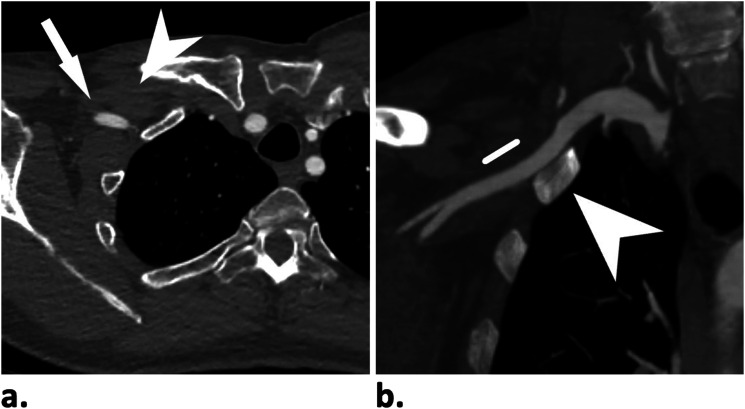

ObjectivesLimited knowledge exists regarding access site complication rates between trans-axillary and trans-brachial approaches with sheath sizes ≥6Fr. We retrospectively reviewed our institution experience with access site complications for percutaneous trans-axillary and trans-brachial arterial interventions using sheath sizes ranging from 6Fr to 10Fr.MethodsWe examined 67 endovascular interventions performed over 18 months, restricted to sheath sizes of 6Fr to 10Fr. Procedures utilizing trans-brachial (41 cases) and trans-axillary (26 cases) approaches under sonographic guidance were included. Cases involving hemodialysis accesses and those requiring surgical cut-down were excluded. The primary outcome measure was the occurrence of major access site complications (SIR grade-II/III) within 30 days, with data collected on hemostasis method, sheath size, and complications. Statistical analysis involved ANCOVA and Fisher's exact tests, with significance set at p < .05.ResultsSuccessful percutaneous arterial access was achieved in all cases using either approach (trans-axillary or trans-brachial). Closure devices were employed in all axillary punctures and in 71% of brachial punctures. Major access site complications occurred in 7 out of 41 cases (17%) in the trans-brachial group and in 4 out of 26 cases (15%) in the trans-axillary group. However, there was no statistically significant difference in complication rates between the two groups, regardless of access site or sheath size.ConclusionTrans-axillary access serves as a safe and effective upper limb access method for percutaneous endovascular procedures requiring sheath size of 7Fr or larger when compared to trans-brachial approach.

Abstract Image